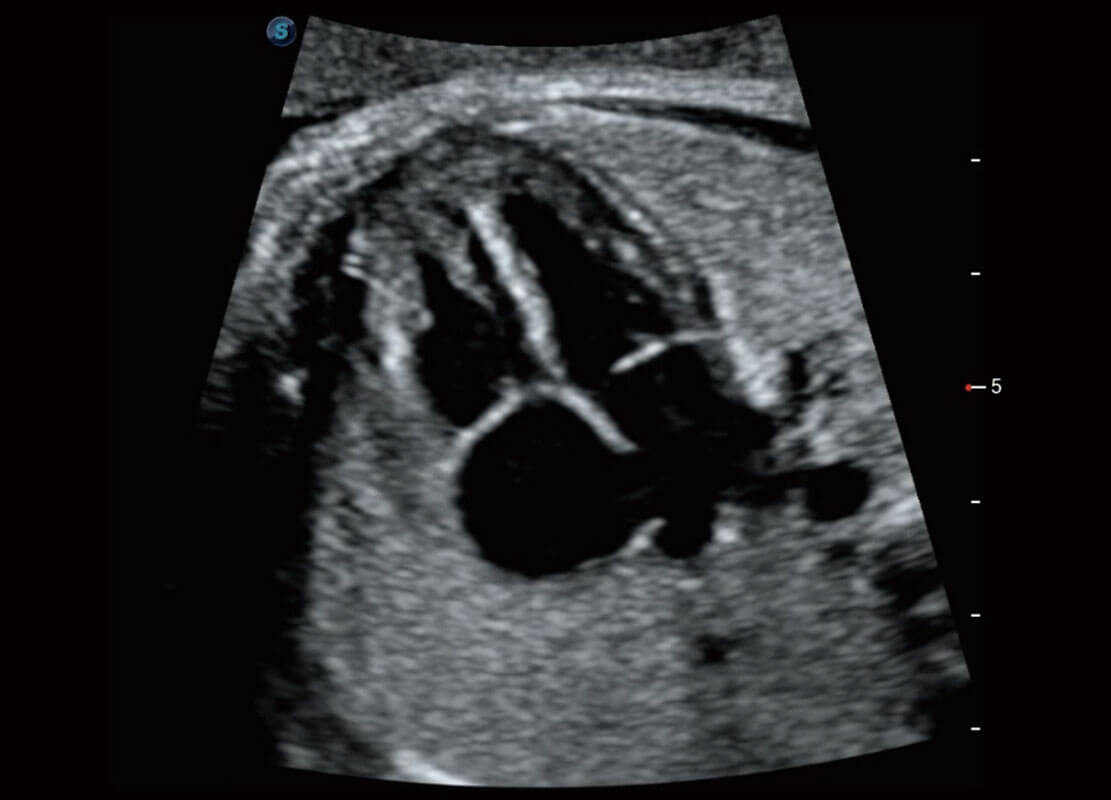

P60提供简单易学易用的高端诊断工具,为您中晚孕筛查提供快速清晰的解剖信息。

1 OFD(HC): 87.03 mm

HC: 251.00 mm

GA: 27w 1d

HC/AC: 96.13 %

2 BPD: 70.56 mm

GA: 28 w 2d

S-Fetus(acq.)

&

S-Fetus(meas.)

S-Fetus能够助您在实时扫查过程中自动识别标准切面、自动测量并录入报告。一个按键,即可快速、高效地获取胎儿生理指标,简化您的产科检查操作。